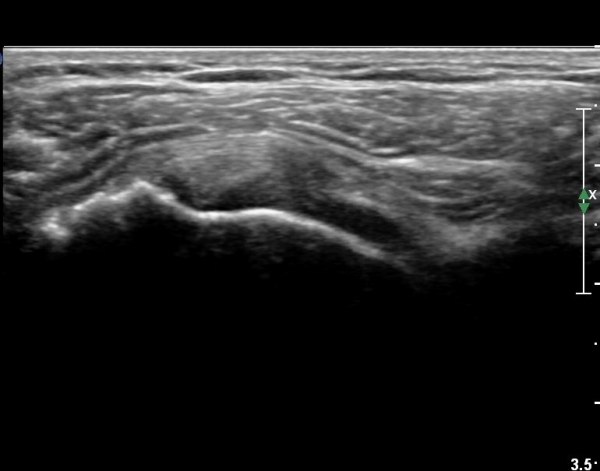

ȸÀü±Ù°³°£°Ý(rotator cuff interval) Ⱦ´Ü¸é°Ë»ç¿¡¼­ ÀÌµÎ¹Ú±Ù°Ç ¿ÜÃø¿¡ ±Ø»ó°ÇÀÌ °üÂûµÇÁö ¾Ê°í

´ë°áÀý Ç¥ÃþÀÇ »À°¡ ¿ïÅüºÒÅüÇÏ°Ô º¯ÇÏ¿´´Ù(±×¸² 1, 2)

ÀÌ´Â ½ÉÇÑ Ãæµ¹ÁõÈıºÀÇ °á°úÀ̰í ȸÀü±Ù°³ ÆÄ¿­À» °­·ÂÈ÷ ¾Ï½ÃÇÏ´Â ¼Ò°ßÀÌ´Ù.